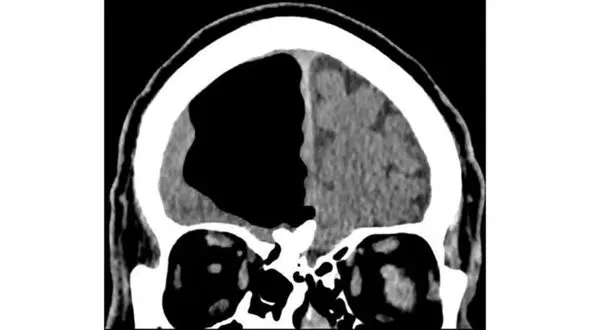

حوادث رکنا: پزشکان با اسکن مغزِ یک مرد ایرلندی به حفرهای به اندازه یک سیب در جمجمه او و فضایی که در واقع مغز او باید قرار داشته باشد، برخورد کردند.